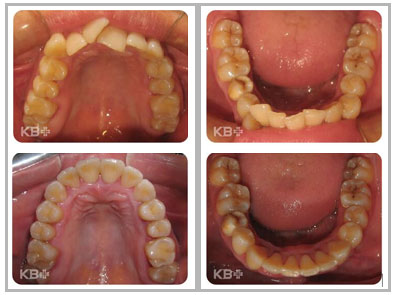

康贝佳口腔医院正畸科主任夏海涛表示:牙列拥挤在错合畸形中较 为常见,分为单纯拥挤和复杂拥挤。

单纯拥挤表现为牙齿因间隙不足而排列错乱,并因此影响到牙弓形态与咬合关系;单纯拥挤可视为牙性错合,一般不伴颌骨及牙弓间关系不调,也少有口颌系统功能异常,磨牙关系中性,面形基本正常。

复杂拥挤时,除牙量不调造成的拥挤之外,还存在颌骨、牙弓间关系不调,并影响到患者的面形,有时还伴有口颌系统功能异常;复杂拥挤时拥挤本身只是一个症状,并不是错合的主要方面。